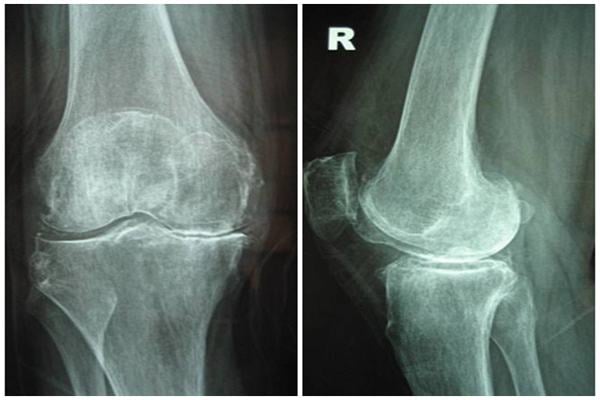

Yếu tố làm tăng khả năng mắc thoái hóa khớp

Thoái hóa khớp là hiện tượng thoái hóa loạn dưỡng của khớp với biểu hiện là sự biến đổi ở bề mặt sụn khớp, hình thành các gai xương. Khi không được phát hiện và điều trị sớm, thoái hóa khớp có thể gây biến dạng khớp. Dưới đây là các yếu tố làm tăng […]